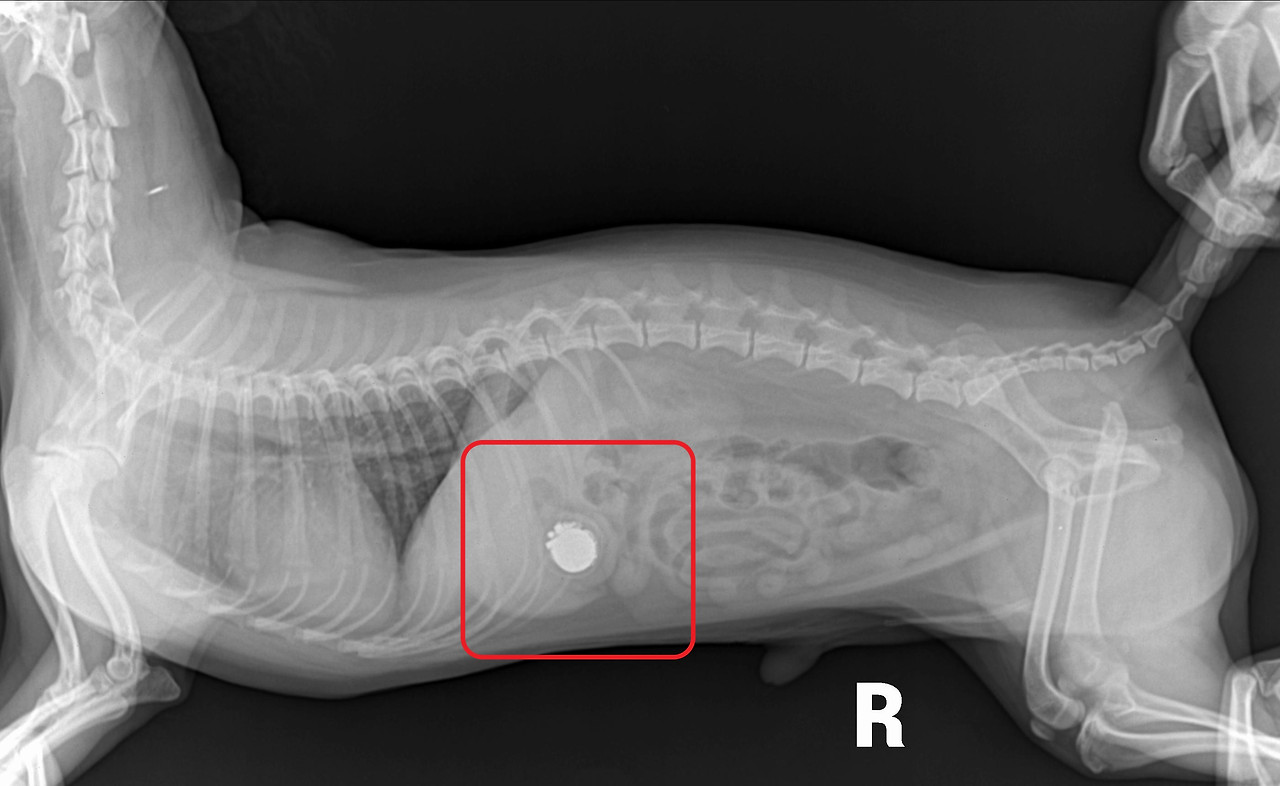

3.jpg

<좌> 식도에 간식이 걸린 경우 <우> 위에 옷핀과 동전이 있는 경우

사진출처 : 24시 센트럴 동물 메디컬센터

"이물을 삼킨 경우에는 어떻게 되나요?"

반려견이 이물을 삼킨 경우에는 반려견의 종류에 따라 다양한 문제를 야기할 수 있습니다.

동전은 구리 중독, 날카로운 플라스틱이나 바늘 등은 위장 천공을 유발하게 됩니다.

덩어리가 있는 이물이라면 소장 폐색으로 응급 수술을 해야 하고

위 내 여러 이물이 정체되어 있으면 만성 위장관 염증을 일으켜서 구토를 하게 됩니다.

이물을 삼킨 경우에는 즉시 병원을 방문해야 하고 평소 집 근처의 24시 동물병원을 알아두는 것이 좋습니다.